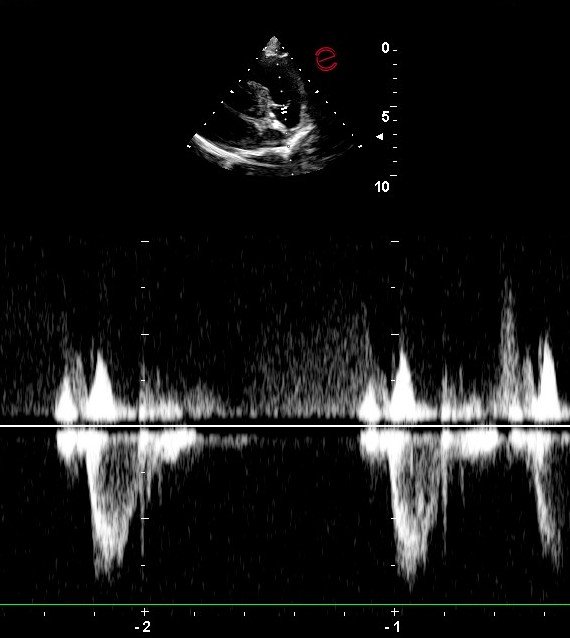

Echocardiogram with Cardiologist Consult

The use of ultrasound technology and skill to evaluate the heart to determine stages of disease relating to:

• valve structure and function

• chamber size, wall thickness, and contractility

• systemic and pulmonary blood pressures , intra-cardiac pressures

All echocardiograms will be digitally referred to a board certified cardiologist for interpretation along with available thoracic radiographs, blood pressure, and ECG.

Referral of cases to a cardiologist may still be recommended depending on the severity of the disease, additional treatment option, or for surgical intervention.